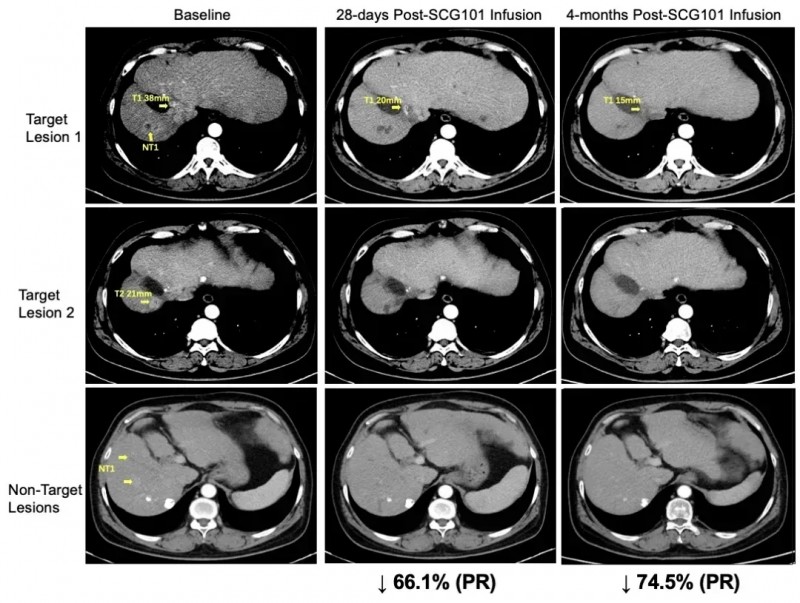

结果显示:该患者在SCG101治疗第28天,肿瘤靶病灶较基线缩小66%,率先达成部分缓解(PR)标准;并在治疗第4个月,肿瘤进一步缩小至74.5%,另有一处病灶更是完全消失(详见下图)。截至数据统计时,患者无进展生存期已超6.9个月,并持续维持缓解状态。

▲图源“SCG”,版权归原作者所有,如无意中侵犯了知识产权,请联系我们删除